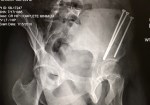

My x-rays looked great. He was really impressed with my progress, recovery and bone growth. So much so that he said I could get my screws out a month early! I was speechless and shocked and then so excited! I really did not expect that. I set a date for March 22nd, so the next time I see him will be for my pre-op appointment for the hardware removal. I’m so ready to have all this behind me!